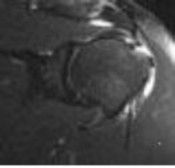

3. # Figure 5 shows the MRI scan of a 35-year-old woman with shoulder pain. What is the most likely diagnosis?

DISCUSSION: The MRI scan shows a coronal oblique view of a partial-

thickness bursal surface supraspinatus tear. Partial-thickness rotator cuff tears are a common cause of shoulder pain, with articular-sided tears two to three times more common than bursal-sided tears. The articular surface of the supraspinatus is intact in this image; therefore, no partial articular or full-thickness tear exists. The superior labrum is seen at the top of the glenoid with no tear. Internal impingement affects the articular surface of the rotator cuff in abduction and external rotation, causing labral tearing and partial articular-sided rotator cuff tears. The Preferred Response to Question # 5 is 3.